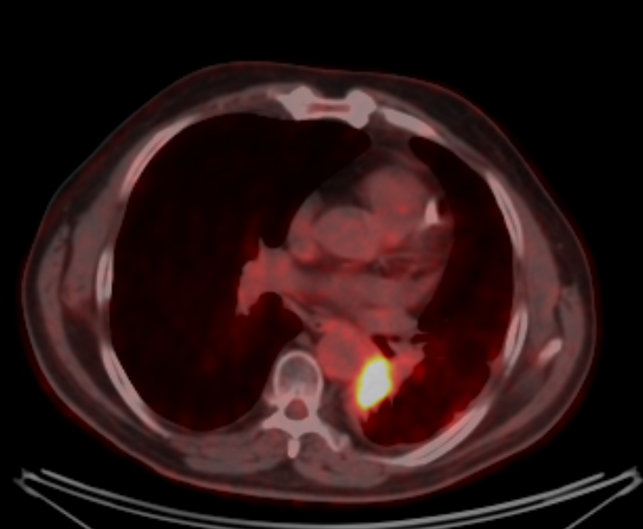

На момент ПЭТ\КТ с 18-ФДГ от 18.10.2022 по сравнению с исследованием от 28.06.2022. отмечается: - уменьшение размеров со снижением метаболической активности образования в воротах левого легкого; - дальнейшее уменьшение размеров и снижение метаболической активности медиастинальных лимфоузлов;